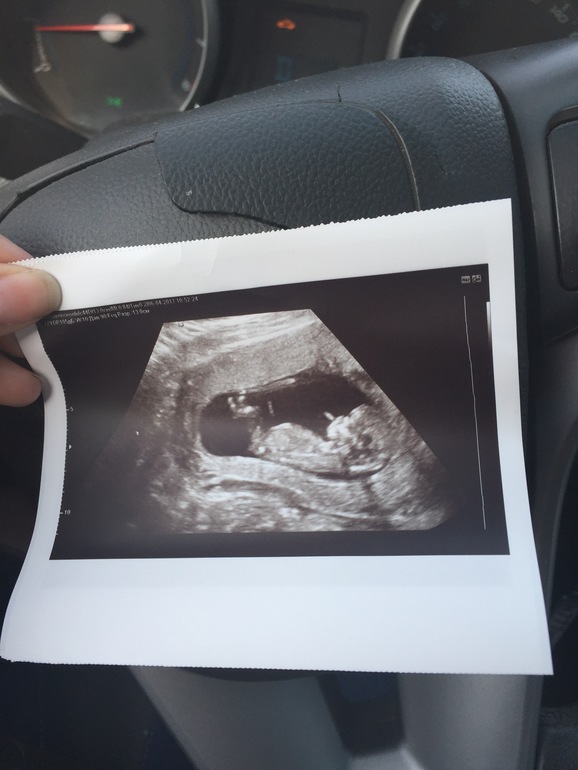

Привет девочки. Вот и прошла я долгожданный скриннинг. Беременность очень желанная. В ноябре была зб, и я сразу начала планировать без лечения. И вот уже конец 12 недельки. По месячным 12.1 , по УЗИ 12,6. Малышик опережает. Долго не могли его намерять, очень активный кувыркался и барагозил в животике. Махал маме ручкой. И у меня будет сын! Она на 90 % сказала. Слишком четко бугорок у него поднят. Узист шикарная. Твп 1,5 носовая косточка 2,3, ктр 64. По УЗИ все хорошо, кровушку сдаю завтра, но заверили что при таких показателях кровь будет не плохой. В общем ждём нашего Мишутку)) муж на 7 небе , мечтал о первом сыне. Не чувствую себя беременной. Токсикоза нет, грудь не увеличилась.Ну и чуть чуть фоточек. Ещё хотела спросить чем вы пользуетесь от растяжек ? Я купила масло джонсонс Бейби , посоветовали что хорошее. А то начинают появляться.